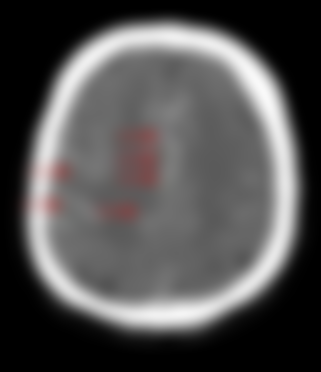

30.急性自發性蛛網膜下腔出血時,緊急做電腦斷層腦部血管造影(brain CT angiography)常見之目的為何?

(A)尋找腦靜脈出血點

(B)尋找破裂的腦動脈瘤

(C)評估腦動脈阻塞狀況

(D)評估腦血管痙攣狀況

AH(Subarachnoid Hemo...

自發性蜘蛛網膜下腔出血的因素通常是因為囊...

蛛網膜下腔出血=SAH在 CT ...

SAH:出血會瀰漫整個腦室 腦迴 及蜘蛛...